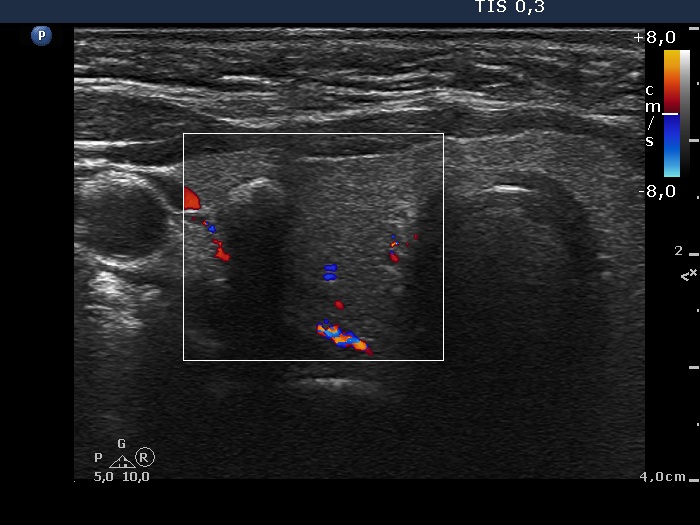

Consecutively operated patients with autoimmune thyroid disease - case 39 (conp 057) (ultrasonographic picture 3)

Right lobe, transverse scan, color Doppler mode. The lesion displays no vascularization.